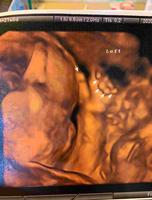

#21W进行了高层次检查、产检、这天也打了流感疫苗。高层次主要是比一般超音波再又更详细的检查宝宝的所有器官,3D或4D基本上就是取悦爸妈的,医师还是都已2D检查为主喔。我们前往(根本就是和安安配合好的)张教授胎儿医学中心,费用就是固定4,500元,到底跟别人有差异在哪我也不清楚,但检查过程是很详细,宝宝也非常配合,在预估的时间内完成,共有两位医师来做讲解,张教授大概就是来做个讲解,他讲的过程感觉就是已经念好几十年,根本不用看萤幕就知道在讲哪个部位,反正他说正常,父母也只有贺贺贺!